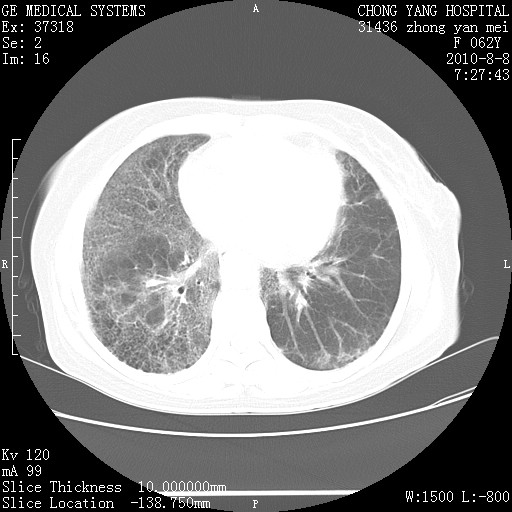

标题: CT28269:F62Y咳嗽胸痛数月。 [打印本页]

标题: CT28269:F62Y咳嗽胸痛数月。

两肺弥漫性间质纤维化伴继发性支扩。

考虑特发性肺间质纤维化

考虑两肺间质性肺炎并肺间质纤维化。

双肺间质纤维化合并感染、肺气肿

双肺间质纤维化

两肺间质纤维化并牵拉性细支气管扩张。

考虑两肺间质性肺炎并肺间质纤维化,肺气囊形成。